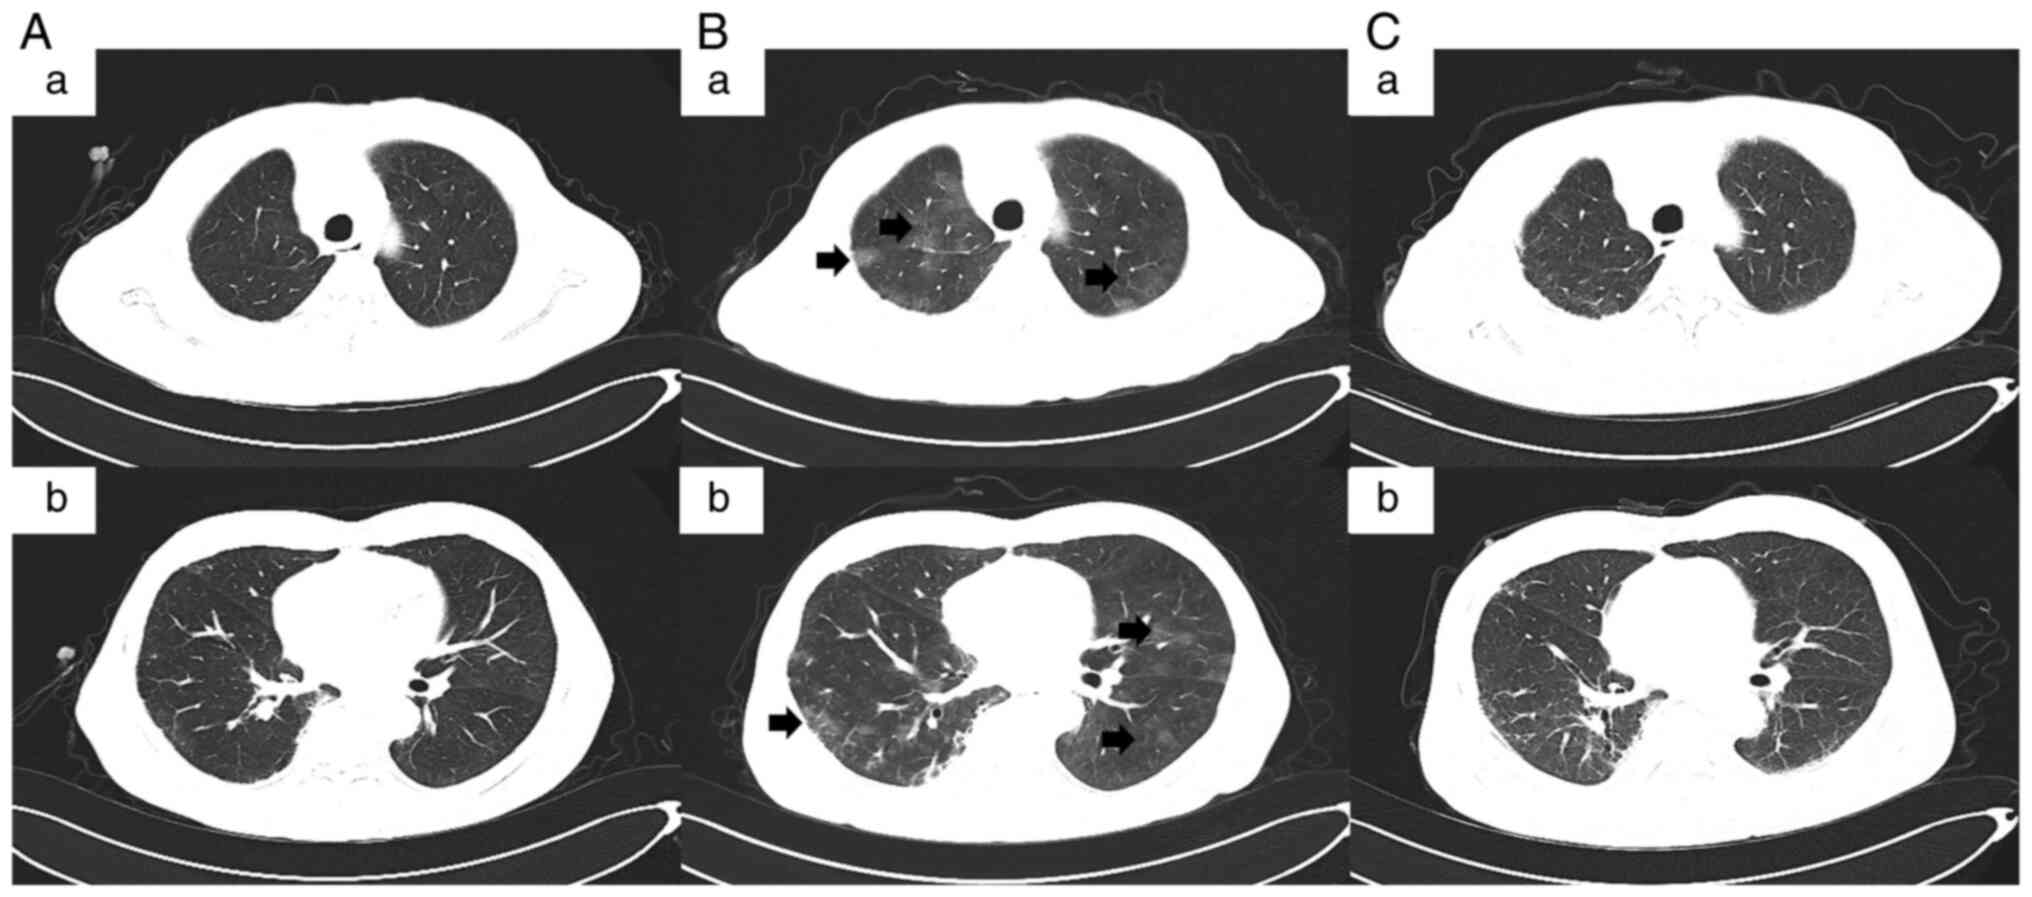

Late‑onset immune checkpoint inhibitor‑related pneumonitis after cessation of sintilimab: A case report and literature review

Immune‑related adverse events following treatment with immune checkpoint inhibitors (ICIs) can occur at any time during therapy, with onset occurring most frequently during the first 3 months of treatment. However, they rarely occur after treatment cessation. An awareness of delayed immune‑related events following the termination of immunotherapy is paramount for optimal tumour management. The present study reports a case of a 69‑year‑old male patient with right lung adenocarcinoma. He suffered from psoriasis for ~40 years and was suspected of developing immune checkpoint inhibitor‑related pneumonitis (CIP) 6 months after the cessation of treatment with the anti‑programmed cell death‑1 receptor antibody sintilimab. The present case study is, to the best of our knowledge, the first case of late‑onset CIP after the cessation of sintilimab. Subsequently, the report also reviews previously reported cases of late‑onset CIP after the cessation of ICI treatment. The present report highlights the finding that CIP can develop, although rarely reported, months or even years after the termination of immunotherapy. Therefore, CIP should always be considered as one of the possibilities and addressed accordingly once the pulmonary infection is ruled out. Careful monitoring, timely diagnosis and administration of corticosteroids are essential in controlling this condition, particularly for patients with pre‑existing autoimmune diseases.